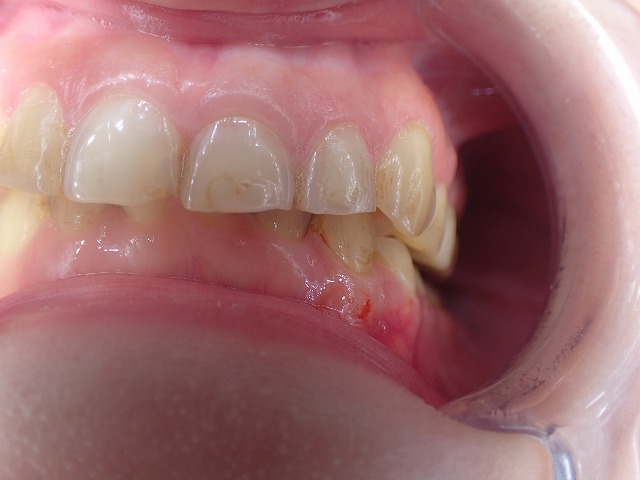

左側のcad/cam冠をジルコニアクラウンに交換

激しい歯ぎしりでCAD/CAM冠が

大きく摩耗しています。

そのため歯と歯の間に隙間ができています。

ジルコニアクラウンに交換

左側のCAD/CAM冠を除去してジルコニアを制作

cad/cam冠などのプラスチック関係の

かぶせ物は、歯肉に炎症を起こす場合がほとんどです。